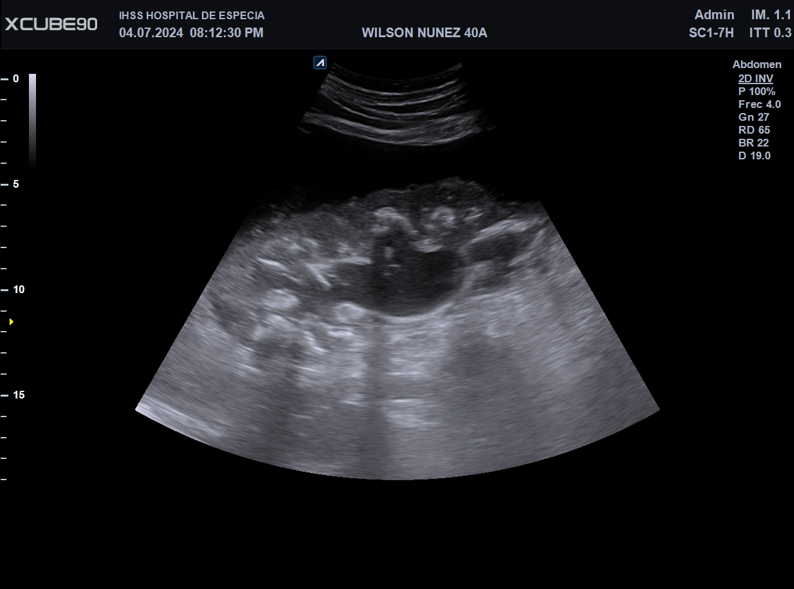

Imagen 1. Corte longitudinal en imagen ecográfica escala 2D de riñón derecho.

Colección perirrenal heterogénea, sin ecos, septos ni tabiques. Aparenta estar contenida dentro de fascia perirrenal con volumen total aproximado de 1400ml.